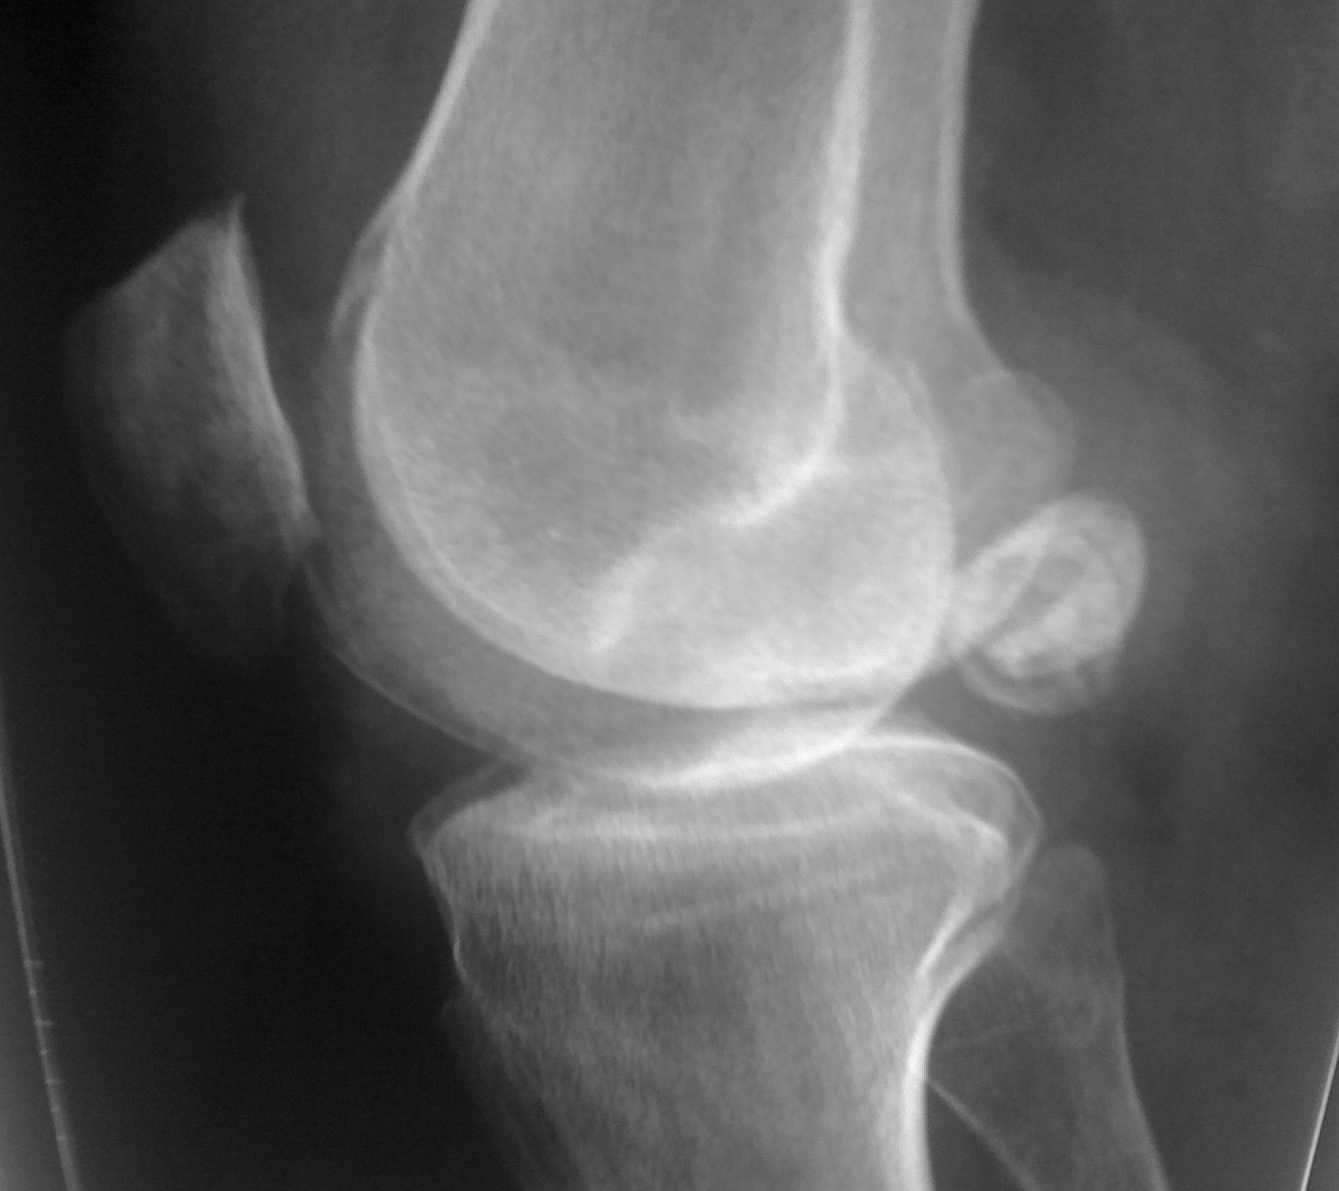

Уважаемые коллеги нужен совет по тактике ведения пациента после артроскопии коленного

сустава

Нужен совет, а точнее ответ на вопрос - нужна повторная операция или

нет? Пациент 37 лет? активный образ жизни мотоцикл, лыжи и остальной

набор развлечений. В марте 2010 оперирован-артроскопия левого коленного

сустава, субтотальная резекция менисков? удаление 3-х свободно лежащих

хондромных тела, тунелизация мыщелков бедренной кости.

Артроскопическая картина гонартроза 3 ст.

С марта по июнь 9 раз пунктировался сустав эвакуировалась по 80-100

мл. светло-желтой синовиальной жидкости без хлопьев и примесей. Посевы

отр. Анализы на инфекцию (хламидии и т.д.) дважды отр. Ревматолог-не

их патология. В общих анализах без отклонений. В приложенном

рентгене-тела в задних отделах как до, так и после операции. Во время

операции-прицельно их искали, но они вне полости сустава, что

подтверждает МРТ. На контрольных ренгенограммах -смещение тел ни на

миллиметр. Зеркальное отображение предыдущих. Болевого синдрома нет.

Единственная жалоба пациента на наличие выпота в суставе. Температурной реакции нет.

Сустав визуально не изменен. не "горяч". Тела в задних отделах не пальпируються. Дважды

параартикулярно вводил дипроспан с интервалом в 4 недели. НВПС. Иммобилизация тутором,

ударная "шокирующая" доза антибиотика-все по нулям. Дайте совет не ужели синовит

поддерживаеться хондромными телами или что то другое. Пациент на повторную операцию 50 на

50. Спасибо! Всех с наступающим профессиональным праздником!!!